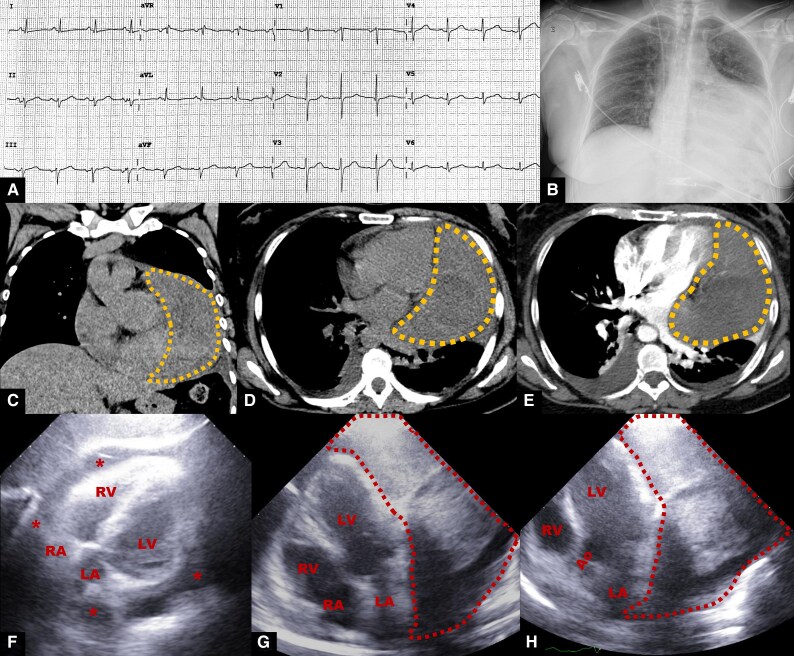

Background: A solitary fibrous tumour (SFT) is a rare fibroblastic tumour, with primary cardiac SFT extremely rare. We report a rare case of a patient presenting with sudden dyspnoea who was diagnosed with a primary cardiac SFT.

Case summary: A 56-year-old woman with a history of diabetes and active smoking presented with sudden dyspnoea. Computed tomography scan revealed a mass adjacent to the left ventricle. In addition to the large pericardial effusion, no signs of cardiac tamponade or valvulopathies were found on echocardiography. The patient underwent open-heart surgery and mass removal, finding a tumour located inside the pericardial sac and attached to the left ventricle's lateral wall; it did not invade other heart structures. Histological and immunohistochemical examination of the mass revealed SFT diagnosis. The patient was discharged from the hospital in full health, and follow-up examinations revealed no evidence of tumour recurrence.

Discussion: Solitary fibrous tumour most commonly occurs in middle-aged patients and is not gender specific. Multimodal imaging is crucial for diagnosing and managing SFT. A definitive diagnosis must be based on both immunohistochemical and histopathological findings. STAT6 immunoexpression is the most reliable marker for histopathology diagnosis. Given the high SFT recurrence rate, follow-up is essential.